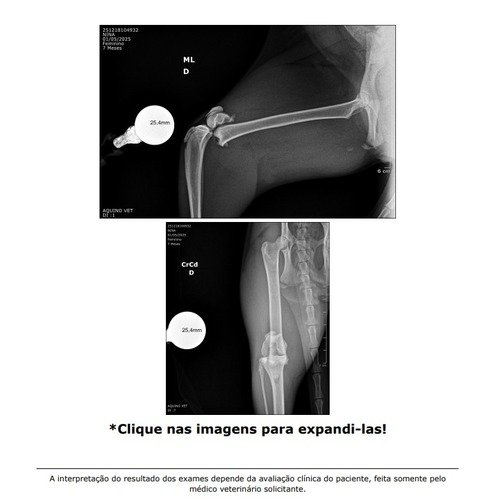

Meu nome é Richard, e Minha gatinha nina foi atropelada…, ela quebrou a perninha e rompeu o Diafragma dela, tive que fazer uma cirurgia de emergencia pois os orgãos dela tinham subido para o torax e estavam comprimindo o coração e pulmão dela, ela quase morreu. O preço da cirurgia foi de R$ 2300,00, e ainda falta a cirurgia da perninha dela que ainda segue quebrada. Todos esses custos são demais para mim bancar, e eu preciso de ajdua para fazer isso… A cirurgia de emergencia foi só para ajeitar o torax dela que estava bem delicado. Mas ainda preciso pagar e planejar a outra cirurgia dela, para a perninha dela, que ainda nem sei quanto vai custar…. Quem puder e quiser ajudar, por favor considere uma doação, qualquer quantia vai me ajudar e muito. Deixarei as imagens do raio X abaixo. E tentarei manter tudo atualizado para acompanharem o progresso.